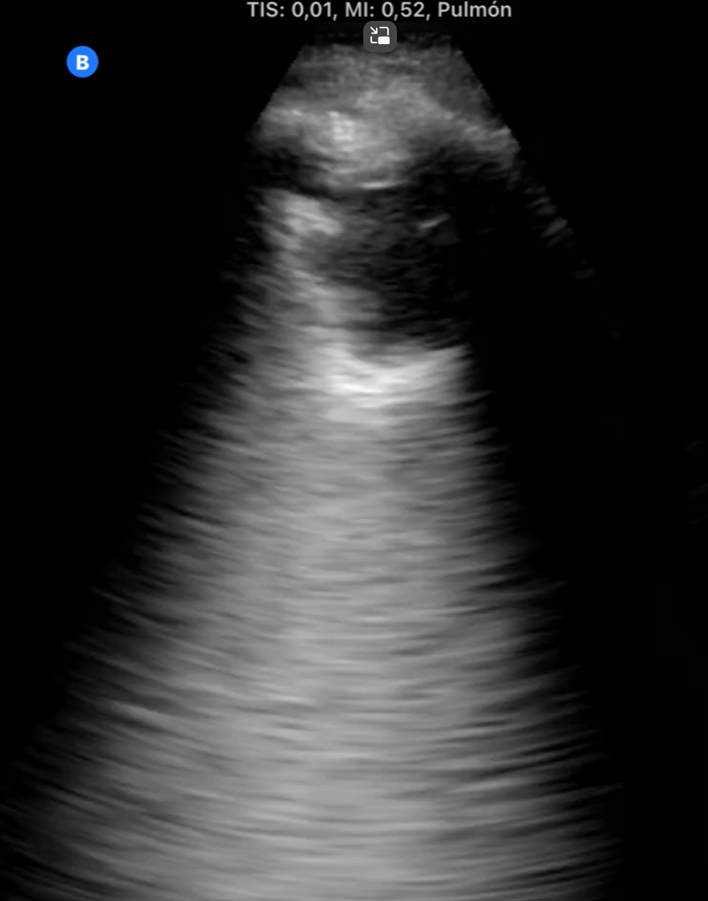

1. Hombre de 82 años que durante consulta de revisión tras caída evidenciamos disnea y taquipnea: TEP agudo bilateral central.